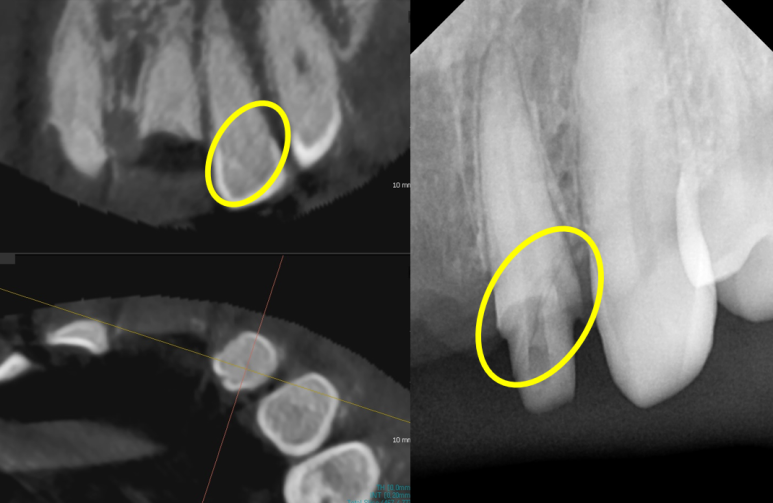

그중 뿌리만 남은 치아의 옆 치아(측절치, #22)도 금이 가있는 것을 발견을 했습니다.

아쉽게도 이 치아에도 금이 가있네요

(맨 우측 사진: 치료 중 X-ray 사진. 치아에 금이 간 것이 선명하게 보입니다.)